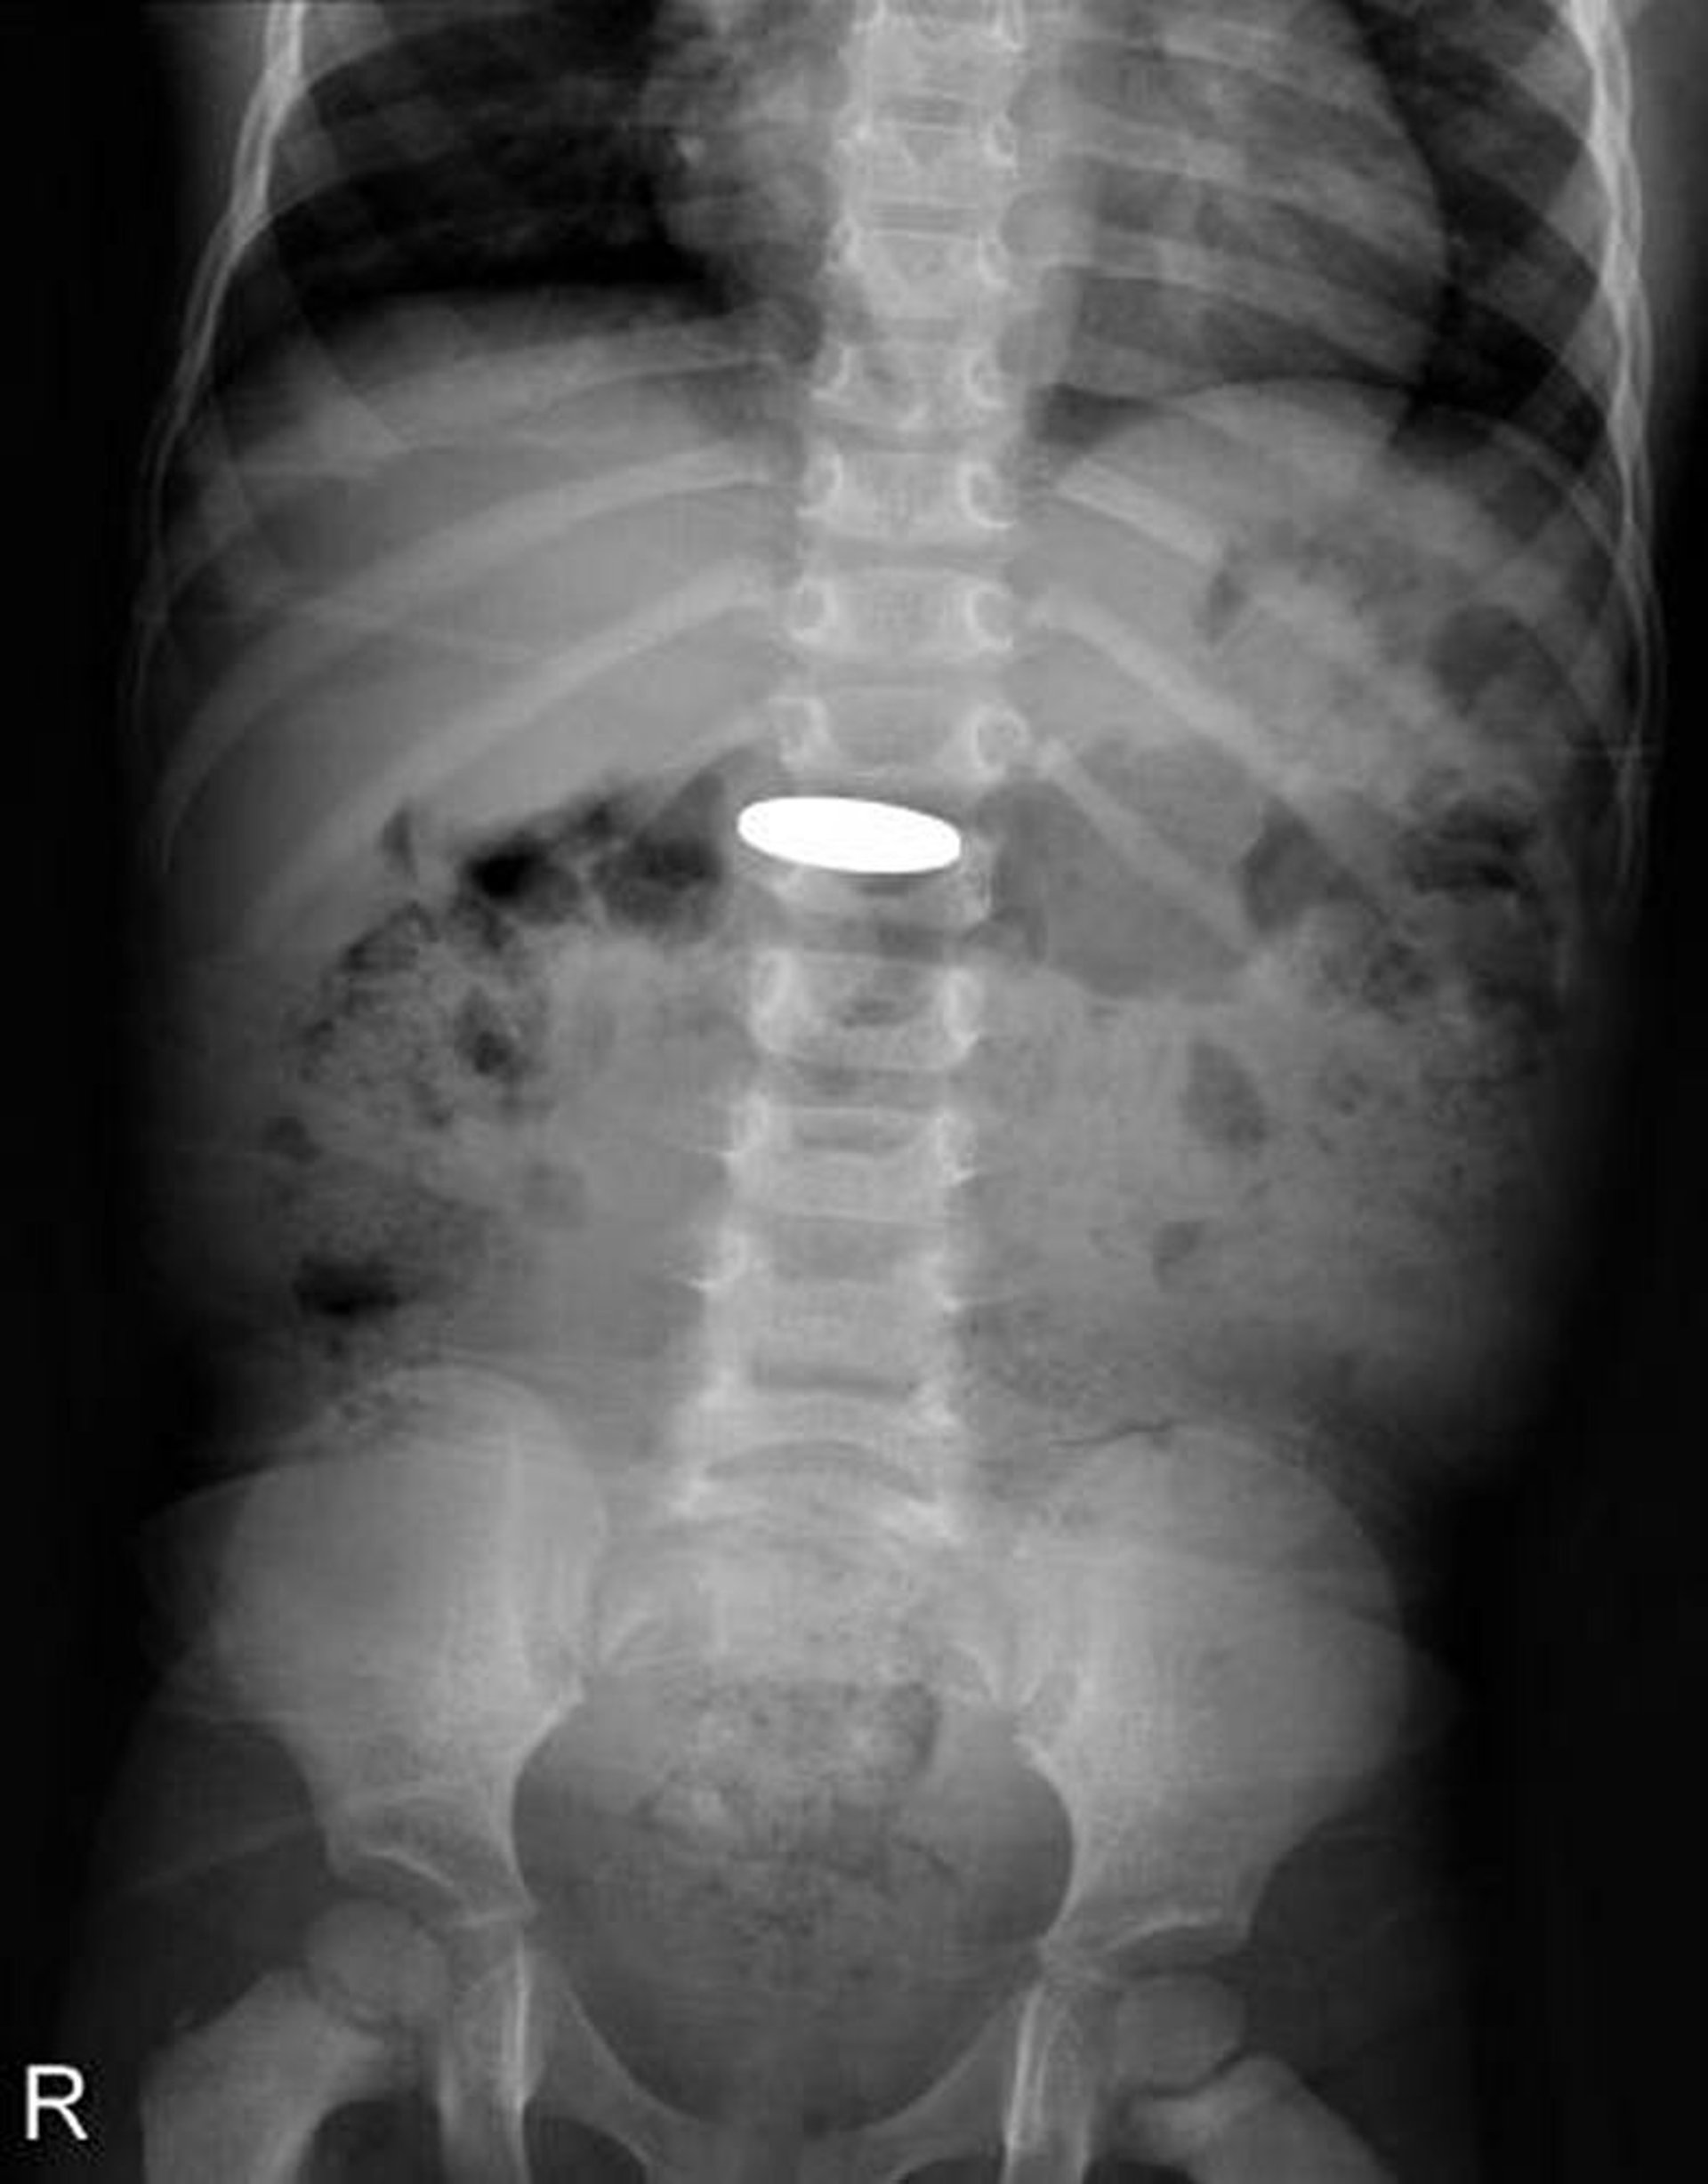

Fremdkörper im Verdauungstrakt (Röntgenaufnahme)

Auf dieser Röntgenaufnahme ist eine Münze zu sehen, die von einem Kleinkind verschluckt wurde.